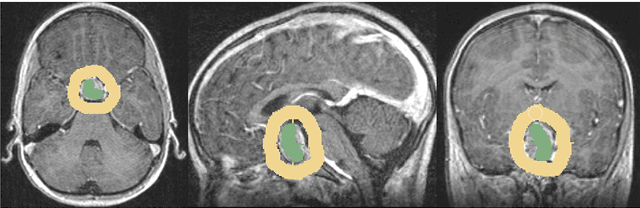

Abstract:The most common sellar lesion is the pituitary adenoma, and sellar tumors are approximately 10-15% of all intracranial neoplasms. Manual slice-by-slice segmentation takes quite some time that can be reduced by using the appropriate algorithms. In this contribution, we present a segmentation method for pituitary adenoma. The method is based on an algorithm that we have applied recently to segmenting glioblastoma multiforme. A modification of this scheme is used for adenoma segmentation that is much harder to perform, due to lack of contrast-enhanced boundaries. In our experimental evaluation, neurosurgeons performed manual slice-by-slice segmentation of ten magnetic resonance imaging (MRI) cases. The segmentations were compared to the segmentation results of the proposed method using the Dice Similarity Coefficient (DSC). The average DSC for all datasets was 75.92% +/- 7.24%. A manual segmentation took about four minutes and our algorithm required about one second.